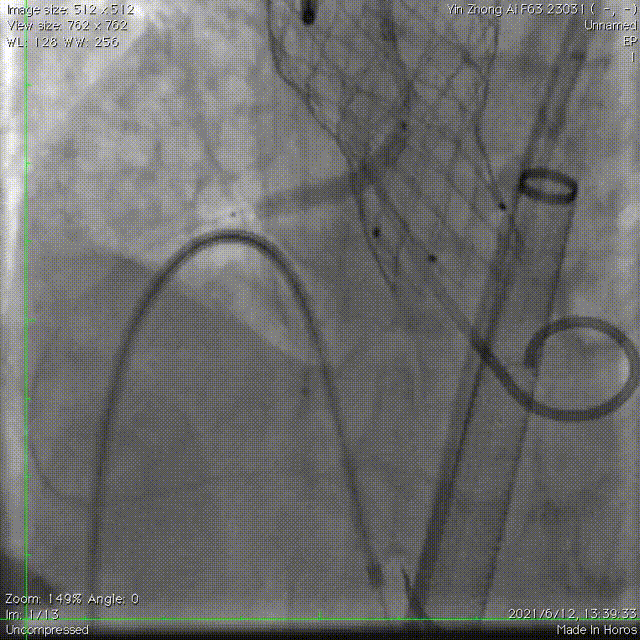

跨瓣成功,采用双侧冠脉双导丝保护 。

在超硬导丝交换后,给与左室充分的时间适应急性AR带来的低血压,上调正性肌力药使血压稳定后,使用20mm球囊扩张,有明显腰征,无瓣周漏,左冠距离远,右冠血流中断。证实术前判断,球扩后患者低血压缓慢恢复,加强正性肌力药支持。